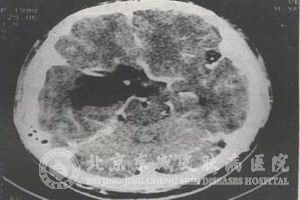

颅中窝表皮囊肿是一种起源于硬脑膜外的损害,以下是北京京城皮肤医院对该症做出的相关介绍。

颅中窝表皮囊肿通常是在硬脑膜外产生的,较后会沿着岩骨嵴逐渐侵入到颅中窝,病症首先就会使三叉神经受累,随后会对其他的一些脑神经进行伤害,损害约有一半的可能性将侵入到天幕下脑桥小脑角内,形成骑跨颅中窝与颅后窝的骑跨型肿瘤。